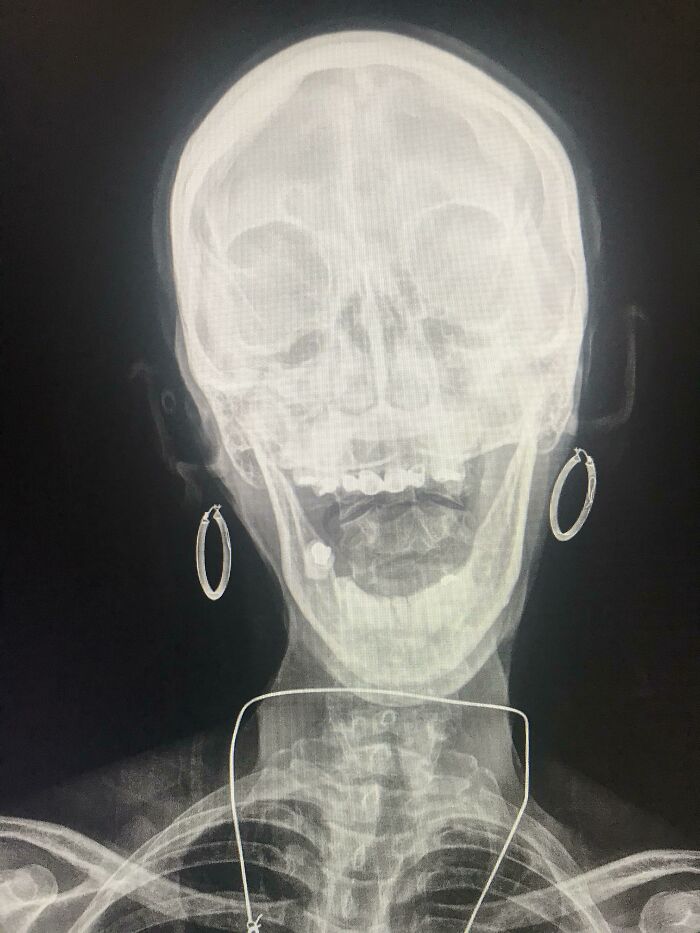

This Xray I Have Of A Pregnant Woman